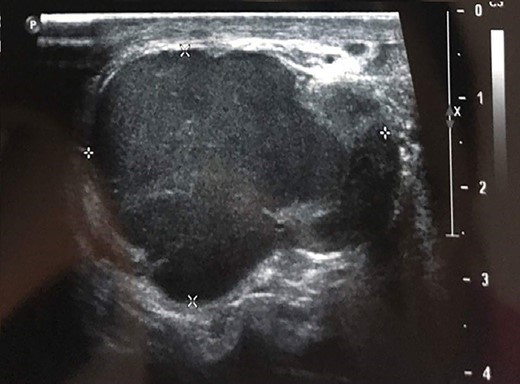

Testicular ultrasonography suggested the diagnosis in all cases, showing a hypoechoic extra testicular scrotal mass highly vascularized at Doppler (Fig. 1).

Testicular ultrasound showing a hypoechoic left extra testicular scrotal mass that is highly vascularized at Doppler.